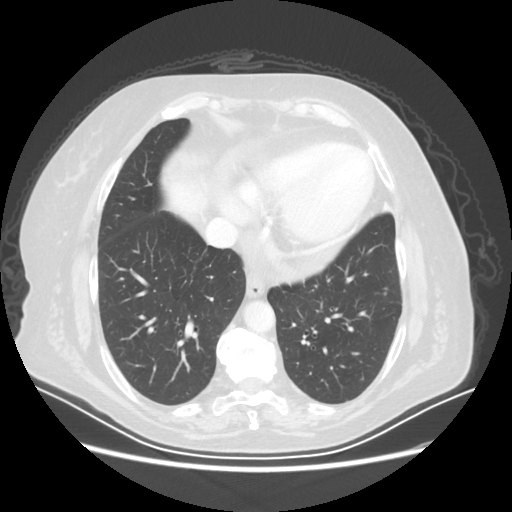

Original VENOUS CT scan

Full window (WL 1023.5, WW 4095 β†’ Low βˆ’1024, High +3071)

Lung window (WL -600, WW 1500 β†’ Low βˆ’1350, High +150)

Mediastinum window (WL 40, WW 400 β†’ Low βˆ’160, High +240)